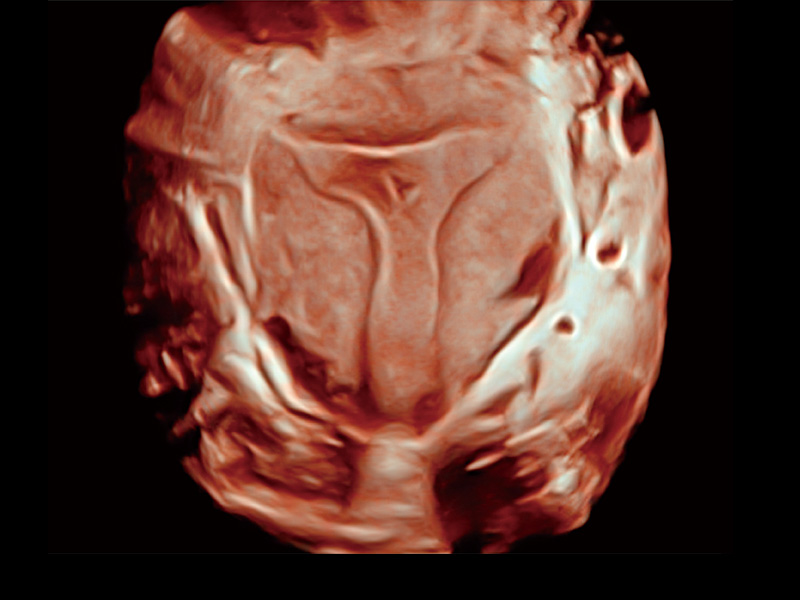

临床图

卵巢多囊样改变

单角子宫